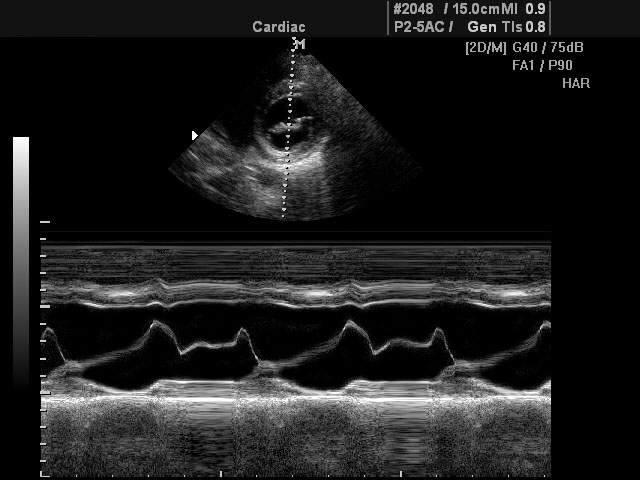

M-режим разработан специально для исследований подвижных структур в реальном времени (от английского motion - движение). Наибольшее применение М-режим нашел в исследовании структур сердца (оценка размеров, сократительной функции сердца, работа клапанного аппарата и т.д.).

При помощи M-эхограммы специалист может количественно оценивать геометрическое смещение подвижных структур и измерять их изменение относительно взаимного положения (просвет в клапанах сердца, изменение размера желудочка и прочее). M-режим зачастую используется вместе с B-режимом (англ. brightness - яркость), во время диагностики врач в B-режиме выбирает необходимый ракурс наблюдения, а затем с помощью курсорной линии на B-эхограмме выбирает направление оси ультразвукового луча для M-режима. Положение датчика фиксируется рукой доктора, после чего включается M-режим.

В М-режиме зондирование периодически повторятся в одном и том же направлении акустического луча. При формировании М-эхограммы в каждом зондировании амплитудная информация об эхо-сигналах с различных глубин отображается в виде отметок различной яркости вдоль вертикальной линии на экране (акустической строки). Следующему зондированию соответствует своя линия, расположенная правее предыдущей, в процессе перемещения столбца с каждым новым зондированием формируется двухмерная М-эхограмма. Положение яркостных отметок по вертикали пропорционально глубине отражающей структуры, например, сердечного клапана.

- Непосредственно отображение изображения только в M-режиме.

- Одновременное отображение двухмерной B-эхограммы и M-эхограммы (использование двух режимов одновременно).